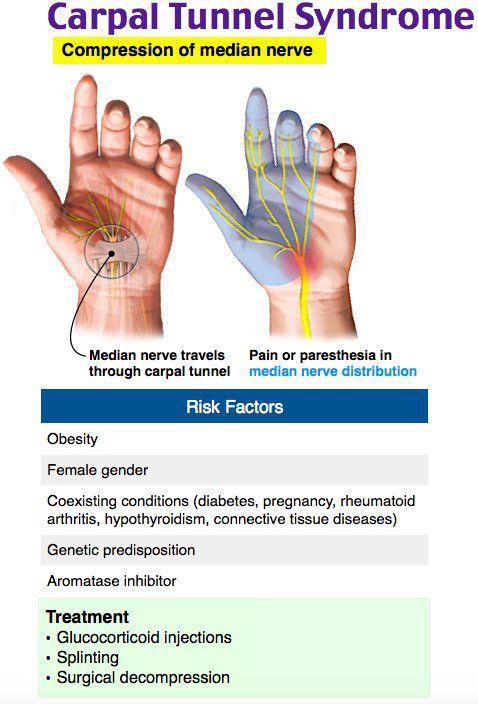

'Carpal tunnel syndrome' is compression of median ...